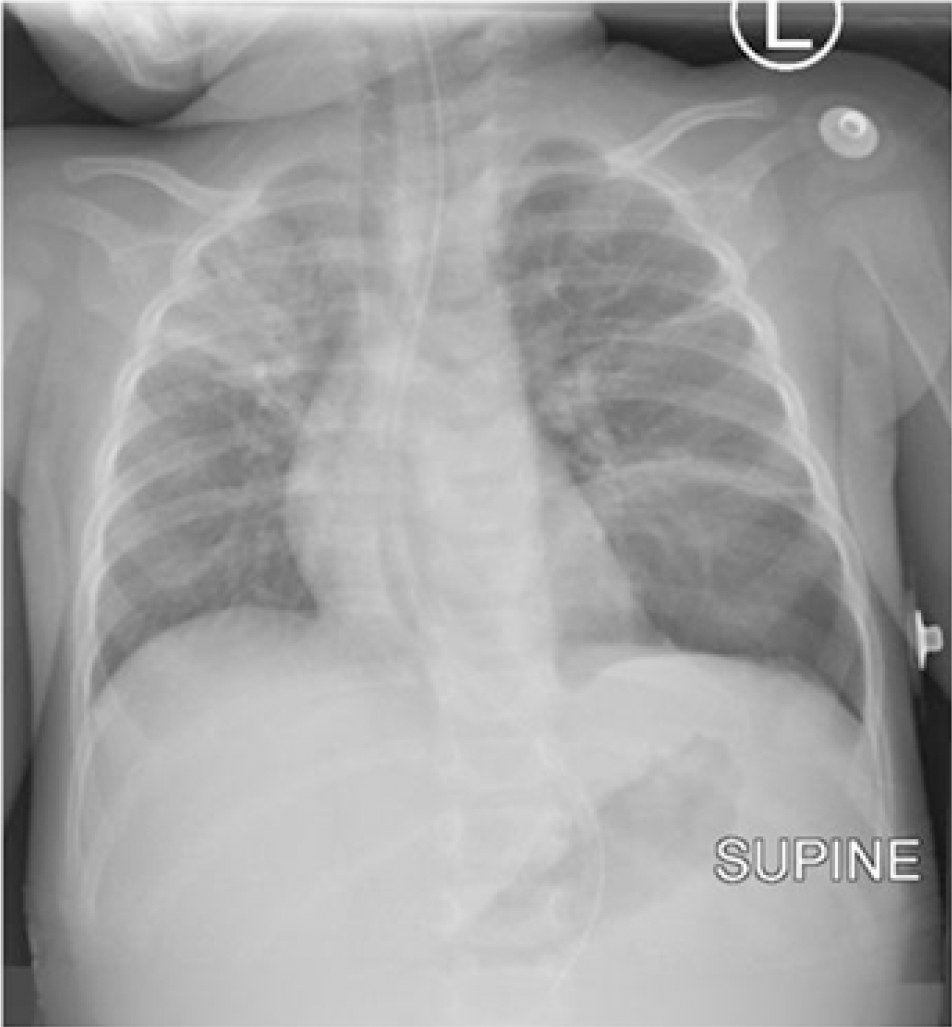

Methods: We present a six-month female baby who presented with clinical features of intestinal obstruction. Ultrasonography of the abdomen revealed gastric volvulus. The baby underwent emergency laparotomy. Gastric volvulus with splenic herniation was encountered through a diaphragmatic hernia.